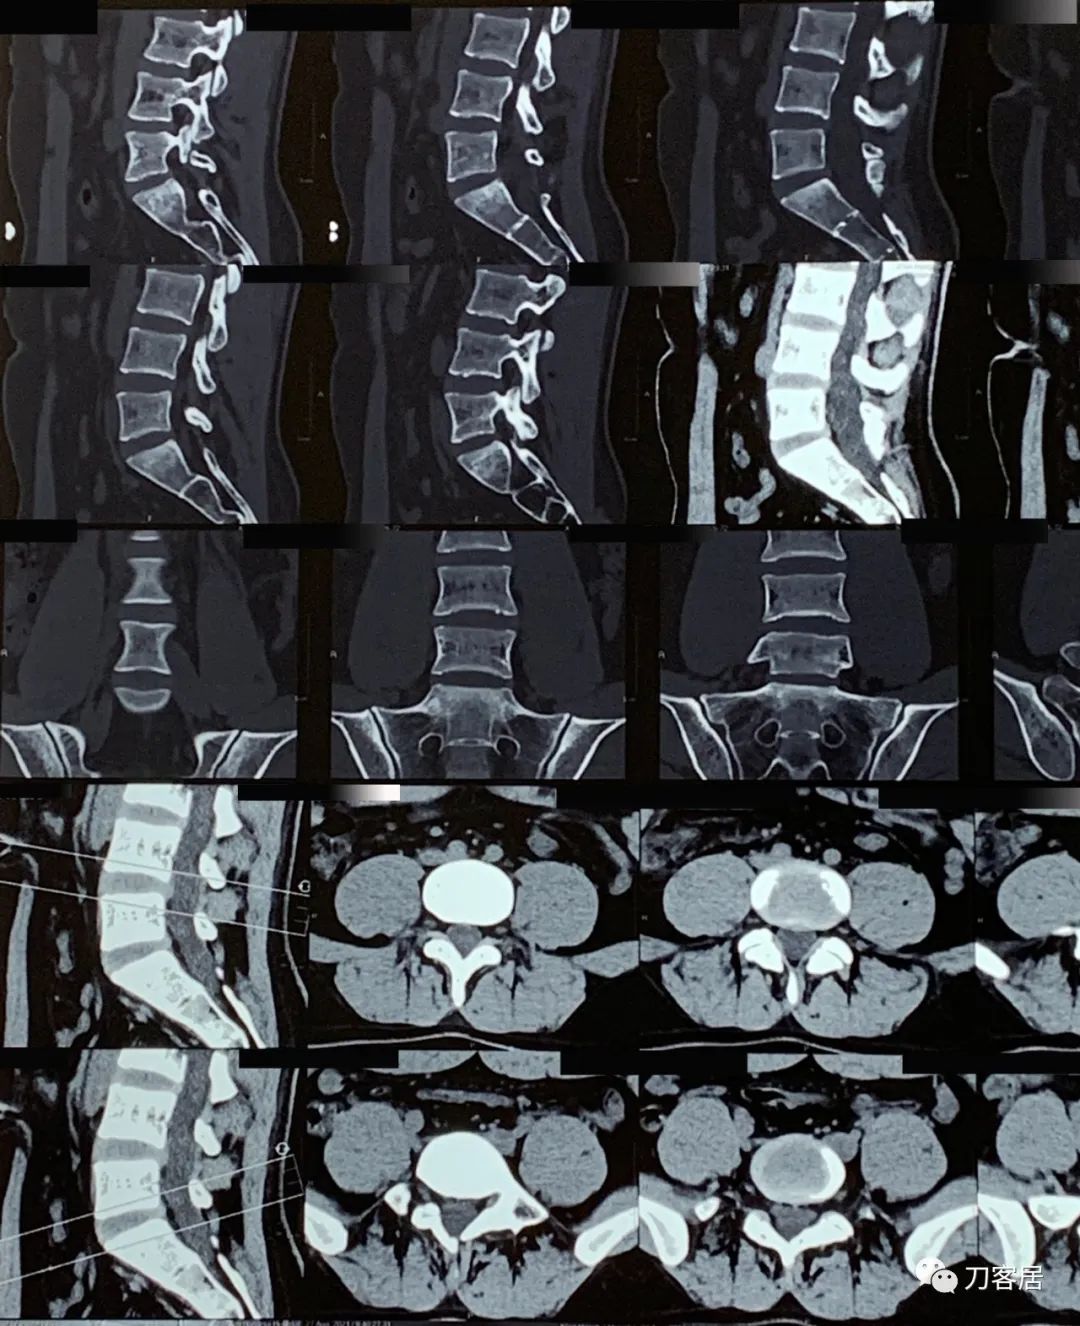

图4. 20210827外院腰椎CT扫描02

图5. 20210827外院腰椎CT扫描报告,提示腰5右侧峡部裂,腰5隐裂,骶1隐裂并棘突游离。

自带腰椎X线片提示右侧峡部裂,外院CT报告右侧腰5峡部裂,腰5骶1隐裂。腰椎MRI及CT检查未见椎间盘突出及椎管狭窄,